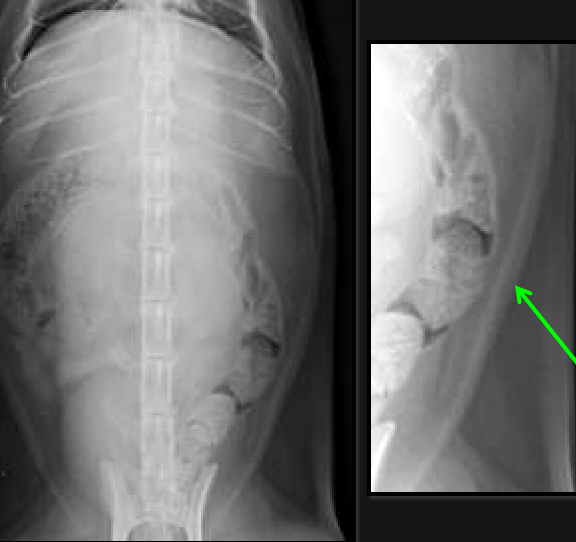

retroperitoneal space

space between dorsal margin of the parietal peritoneum and the abdominal wall

hypaxial muscles and kidneys

retroperitoneal structures

Hypaxial muscles

kidneys